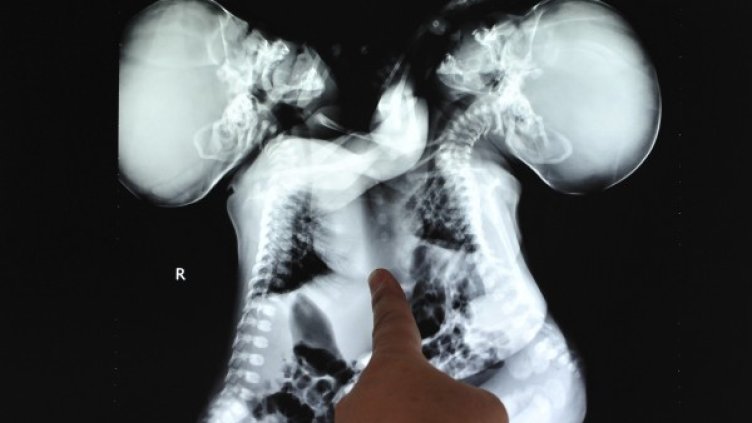

Петмесечните Картър и Конър Мирабал са родени свързани в корема и долната част на гръдния кош, с общ черен дроб и част от тънкото черво.

В операцията са участвали трима хирурзи и петима анестезиолози. Вчера момчетата са били в критично, но стабилно състояние.